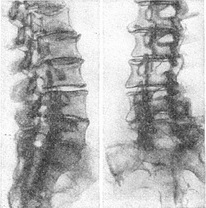

Дегенеративні процеси в хребті - найбільш часта знахідка при рентгенологічному дослідженні. Слід розрізняти деформуючий спондильоз (освіта клювовидных остеофітів на тілах хребців), міжхребцевий остеохондроз (звуження міжхребцевих щілин з крайовими остеофітами) і спондилоартроз (дегенеративна деформація суглобів П.). Нерідко всі ці три стани комбінуються, проте найбільше значення мають дегенеративні зміни в міжхребцевих дисках як причина сдавлений корінців і вторинних радикулоплекситов. Знімки в косих положеннях, томографія та функціональна рентгенографія дають у цьому відношенні дуже цінну інформацію (рис. 34).

![]() Рис. 34. Виражені дегенеративні зміни тіл суглобів і дисків хребців (зліва полубоковая проекція, праворуч бокова проекція). Рентгенограма полумацерированного препарату поперекового і крижового відділів хребта. |